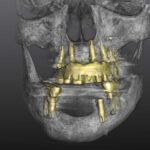

Nutzen des digitalen Workflows bei der prothetischen Rekonstruktion kompromittierter und gesunder Patienten

Prof. Dr. Dr. Walter Lückerath, Bonn